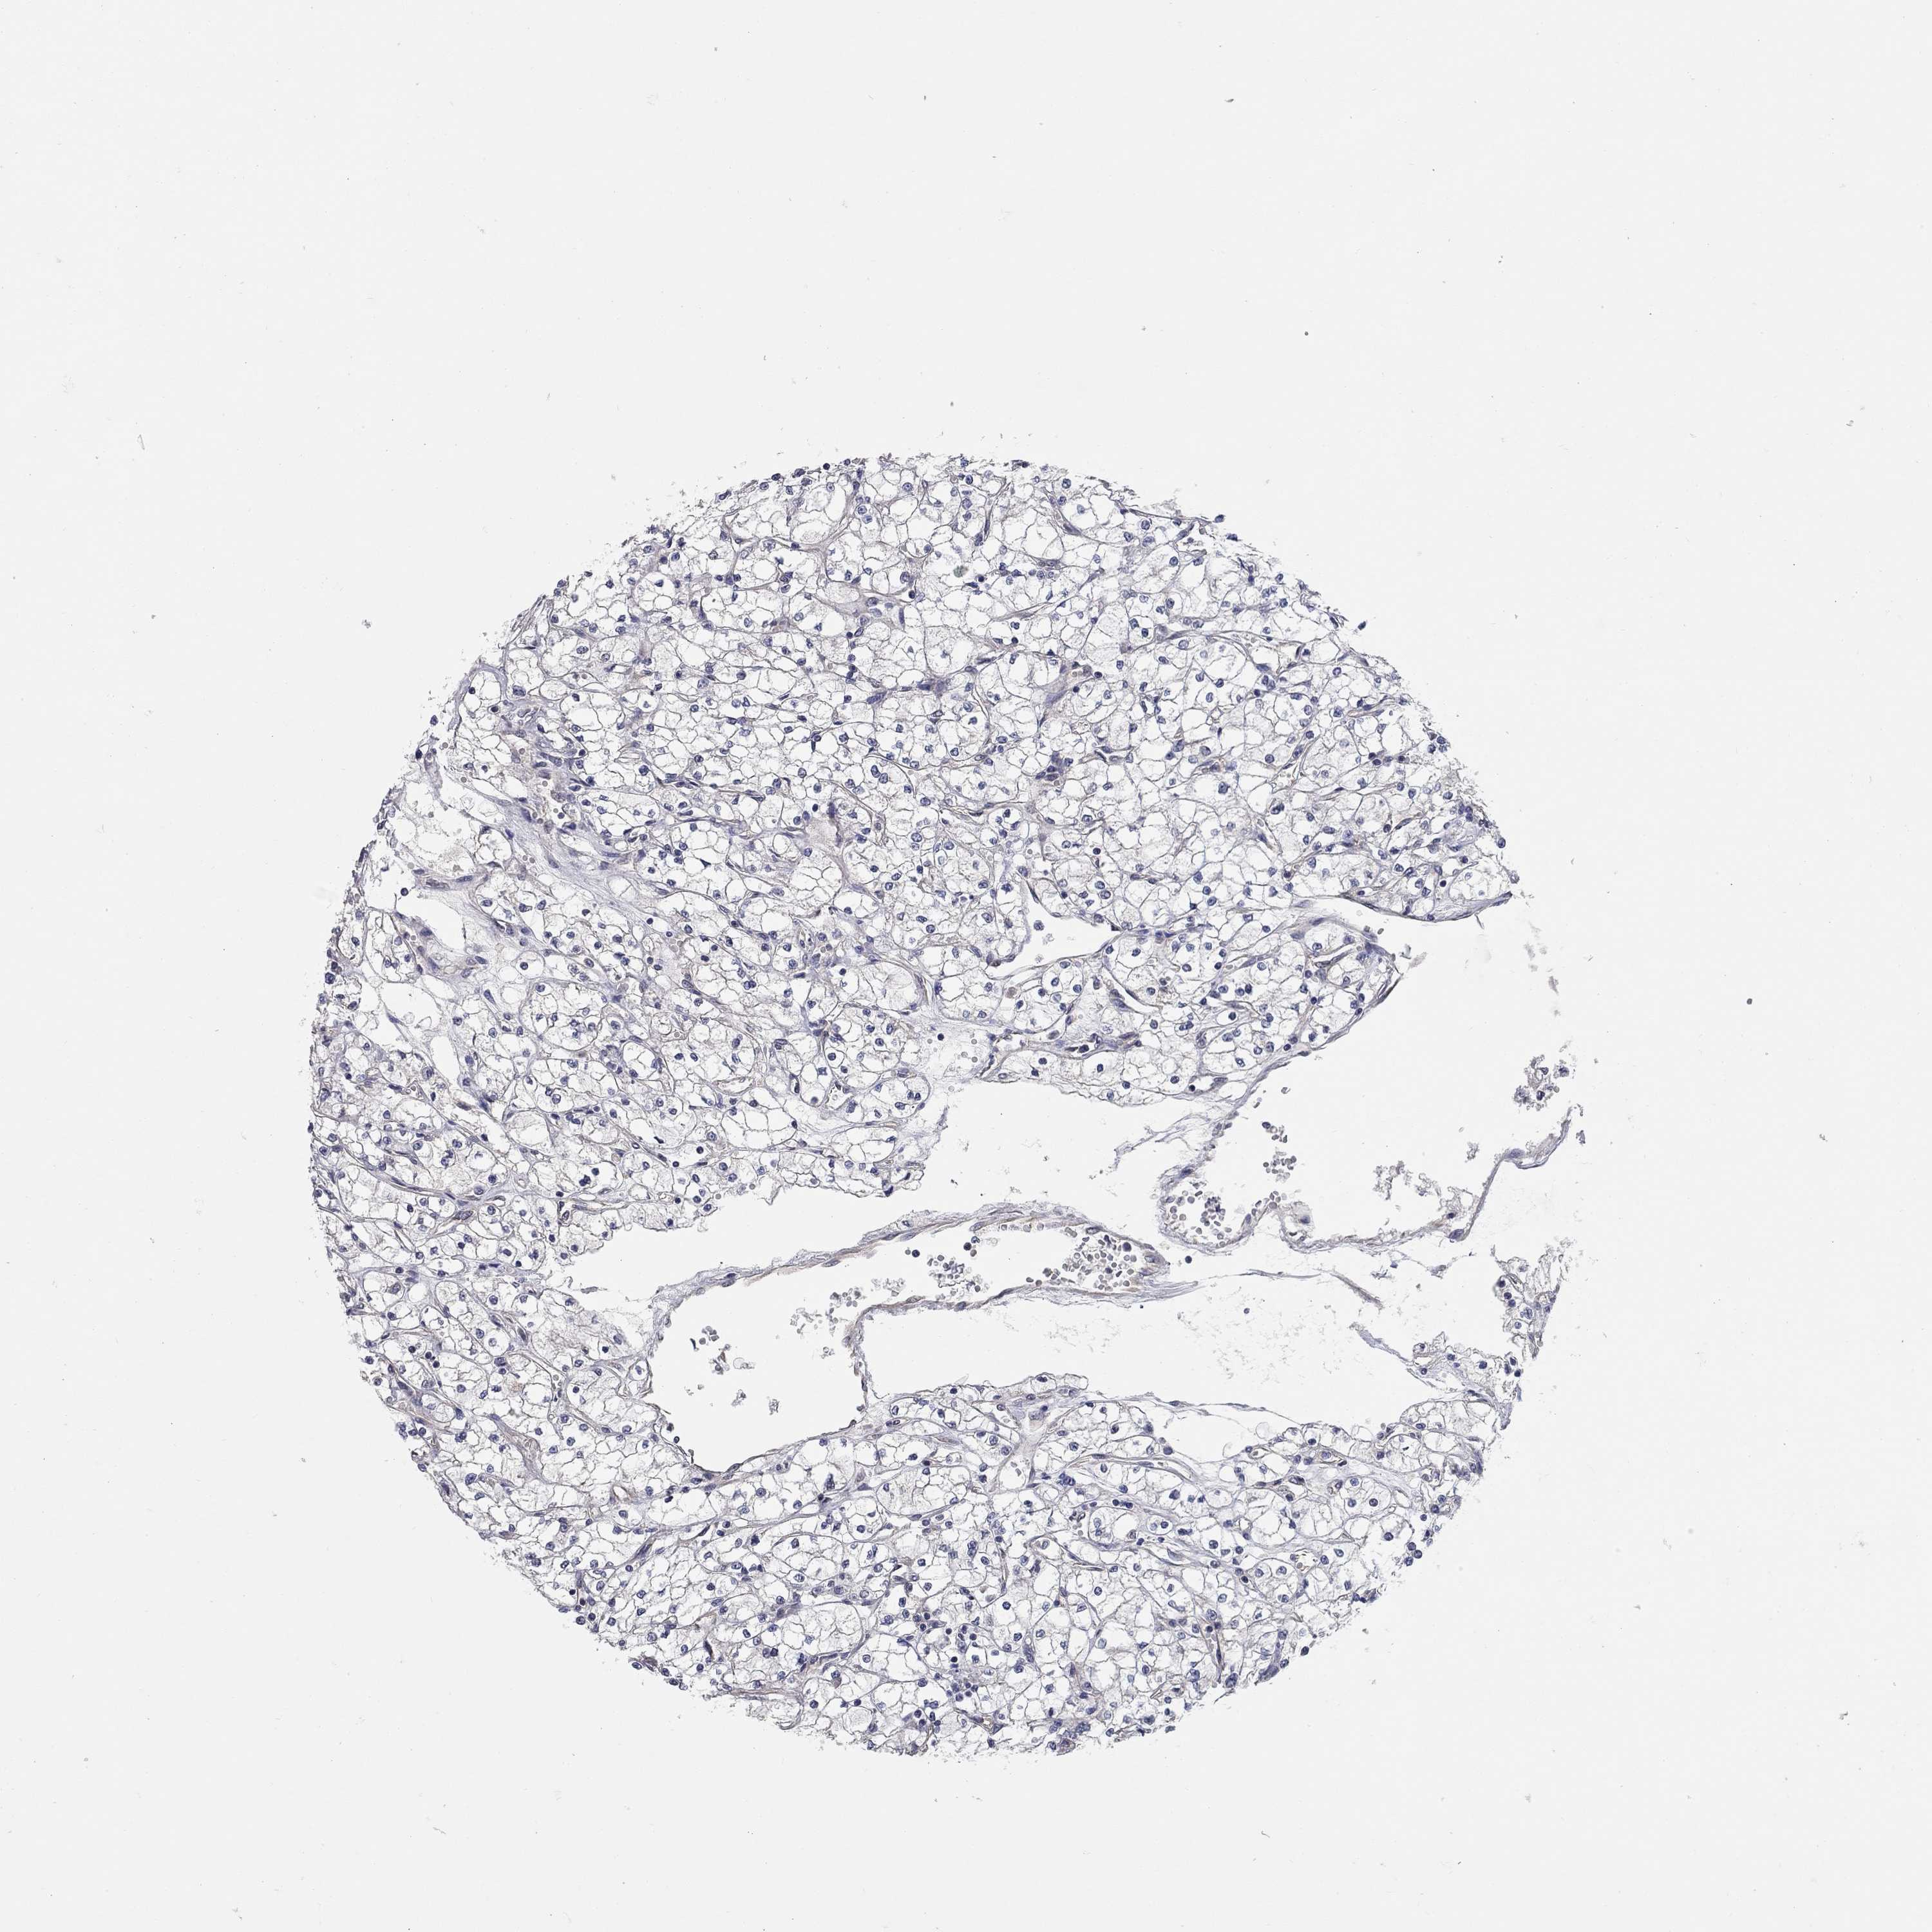

KIDNEY RENAL PAPILLARY CELL CARCINOMA (TCGA) - Interactive survival scatter ploti

The Survival Scatter plot shows the clinical status (i.e. dead or alive) for all individuals in the patient cohort, based on the same data that underlies the corresponding Kaplan-Meier plots. Patients that are alive at last time for follow-up are shown in blue and patients who have died during the study are shown in red.

The x-axis shows the expression levels (FPKM) of the investigated gene in the tumor tissue at the time of diagnosis. The y-axis shows the follow-up time after diagnosis (years). Both axes are complimented with kernel density curves demonstrating the data density over the axes. The top density plot shows the expression levels (FPKM) distribution among dead (red) and alive patients (blue). The right density plot shows the data density of the survived years of dead patients with high and low expression levels respectively, stratified using the cutoff indicated by the vertical dashed line through the Survival Scatter plot. This cutoff is automatically defined based on the FPKM cutoff that minimizes the p-score. The cutoff can be changed by dragging the vertical line or by entering a cutoff value in the square labeled "Current cut-off".

Under the Survival Scatter plot the p-score landscape (black curve; left axis) is shown together with dead median separation (red curve; right axis). Dead median separation is the difference in median mRNA expression between patients who have died with high and low expression, respectively. It is calculated as follows: median FPKM expression of dead patients with high expression - median FPKM expression of dead patients with low expression. This is intended to aid the user in visually exploring custom cutoffs and the associated p-scores and dead median separation.

Individual patient data is displayed and can be filtered by clicking on one or more of the category buttons on the top of the page. Categories describing expression level and patient information include: high, low, alive, dead, female, male and tumor stages. The scale of the x-axis can be toggled between linear and log-scale by clicking on the "x log" button. Mouse-over function shows TCGA ID, patient information and mRNA expression (FPKM) for each patient.

& Survival analysisi

Kaplan-Meier plots summarize results from analysis of correlation between mRNA expression level and patient survival. Patients were divided based on level of expression into one of the two groups "low" (under cut off) or "high" (over cut off). X-axis shows time for survival (years) and y-axis shows the probability of survival, where 1.0 corresponds to 100 percent.

WASF3 is not prognostic in Kidney Renal Papillary Cell Carcinoma (TCGA)

Best expression cut offi

Based on the FPKM value of each gene, patients were classified into two groups and association between prognosis (survival) and gene expression (FPKM) was examined. The best expression cut-off refers the FPKM value that yields maximal difference with regard to survival between the two groups at the lowest log-rank P-value. Best expression cut-off was selected based on survival analysis .

When clicking on this number, the vertical dashed line indicating cut-off, the interactive survival plot, and the Kaplan-Meier curve will be adjusted to show results based on the best expression cut-off.

: 3.16